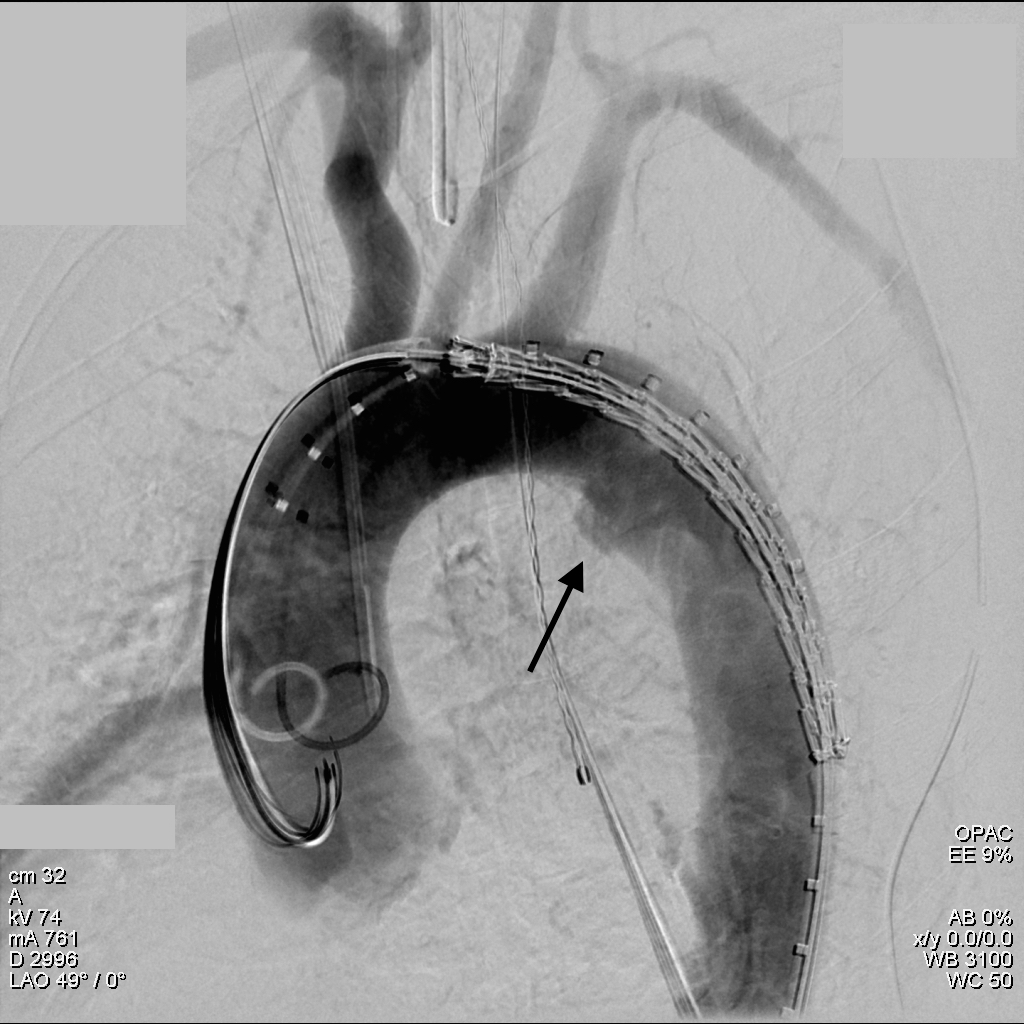

The common femoral endarterectomy is done from its distal most point and the Vollmer ring is used to mobilize the plaque. A Moll Ring Cutter (LeMaitre Vascular) is then used to cut the plaque.

The plaque is extracted and re-establishes patency of the EIA.

The plaque end point is typically treated with a stent -in this case, the common iliac plaque was also treated.